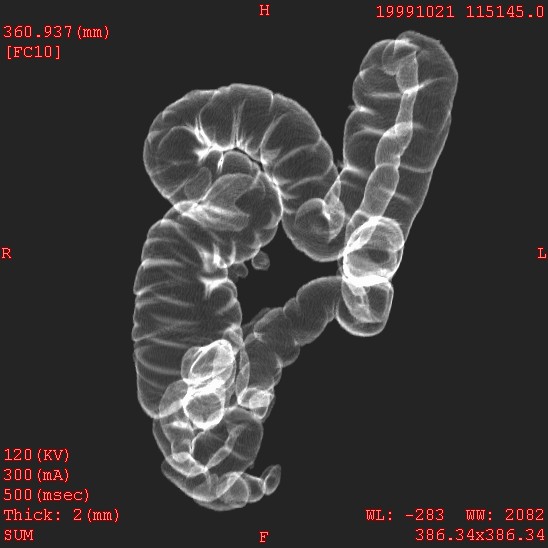

Diverticulosis: Virtual

colonography, 47y, femele

Plain CT, 0.5-sec/rotation,

2-mm x 4, 120kV, 150mAs

Ray sum display, RAO view

Data acquired and processed

by Kei Takase M.D.